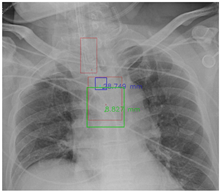

This paper was approved by the institutional review board (IRB) of the National Cheng Kung University (NCKU) Hospital (IRB number: A-ER-108-305). The chest radiograph dataset provided by NCKU Hospital includes 1,870 portable chest radiographs of intubated ICU patients in DICOM format and the ground truth (GT) annotations were labeled by two board-certified intensivists. The GT ETT was labelled by four points ( P 1 4 ), and the GT tracheal bifurcation was labelled by nine points ( P 5 13 ), as shown in Figure 6a. The purpose of this paper was to detect the malposition by locating the ETT tip and the Carina. Therefore, this paper adopted two boxes with a size of 300 × 300 to label the feature point of the ETT tip which was the middle point of P 2 and P 3 , and the feature point of the Carina which was P 9 (the feature point of ETT tip and Carina are at the center of the boxes). Furthermore, the 13 points were corrected to be sequential for generating the GT mask. In summarize, the GT became Figure 6b. In Figure 6b, the green nodes denote the original points labeled by the intensivists, the blue nodes denote the ETT tip and Carina, the green boxes denote the GT bboxes of ETT and tracheal bifurcation, the blue boxes denote the GT bboxes of ETT tip and Carina, and the red polygons denote the GT mask of ETT and tracheal bifurcation. Finally, this paper used extra 150 chest radiographs to validate the proposed approach.

Figure 6. Ground Truth. (a) Original ground truth. (b) Pre-processed ground truth.

Diagnostics 12 01913 g006